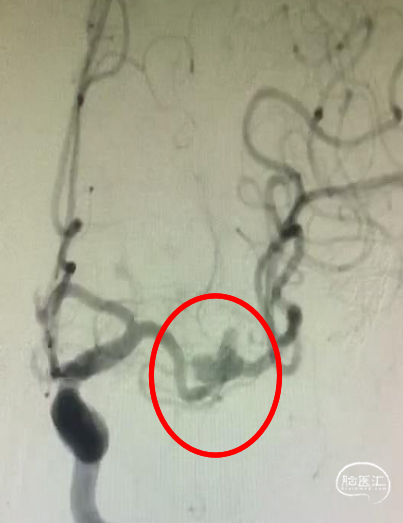

术后半年,患者于当地医院复查DSA提示:左侧大脑中动脉动脉瘤复发(图6)。

图6. 术后半年复查DSA提示动脉瘤复发。